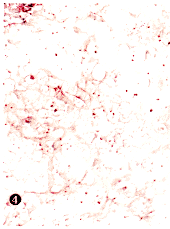

图4 裸鼠移植瘤中的凋亡小体(×50)

Fig.4 Apoptotic bodies seen in nude mice transplant

Showing a lot of apoptotic bodies on the slide stained with TUNEL(×50)

CNE-1移植瘤分化较好,在HE染色下细胞分界较清楚,有时可见细胞间桥和个别角化细胞(插页1图1),而CNE-2移植瘤则分化较差,细胞分界不清楚,无细胞间桥和个别角化细胞(插页1图2)。CNE-1及CNE-2各代裸鼠移植瘤组织在HE染色下均可见到多灶性肿瘤细胞死亡。细胞死亡灶中有“皱缩性坏死”(“shrinkage necrosis”)和凝固性坏死两种形态,而常以“皱缩性坏死”为主(插页1图3)。“皱缩性坏死”的细胞相互分离,体积缩小,胞浆高度嗜酸性,内含1~2个固缩而深染的核,少数细胞甚至不含核(插页1图3)。在TUNEL染色下,这些“皱缩性坏死”的细胞呈强阳性的末端标记信号。凝固性坏死细胞轮廓尚存,胞浆染色较浅,核已消失(插页1图3)。在所谓非细胞死亡灶的HE染色下仍可见到少数位于细胞间和被瘤细胞吞噬的凋亡小体(插页1图2)。凋亡小体表现为不含或含染色质的微小嗜酸性小体,被吞噬在细胞内的凋亡小体旁常有一个空晕。在TUNEL染色下除了这些凋亡小体呈阳性信号外,许多HE染色下被忽视的凋亡小体都可被检测到(插页1图4)。每个高倍视野(10×40)至少有100个凋亡小体信号。